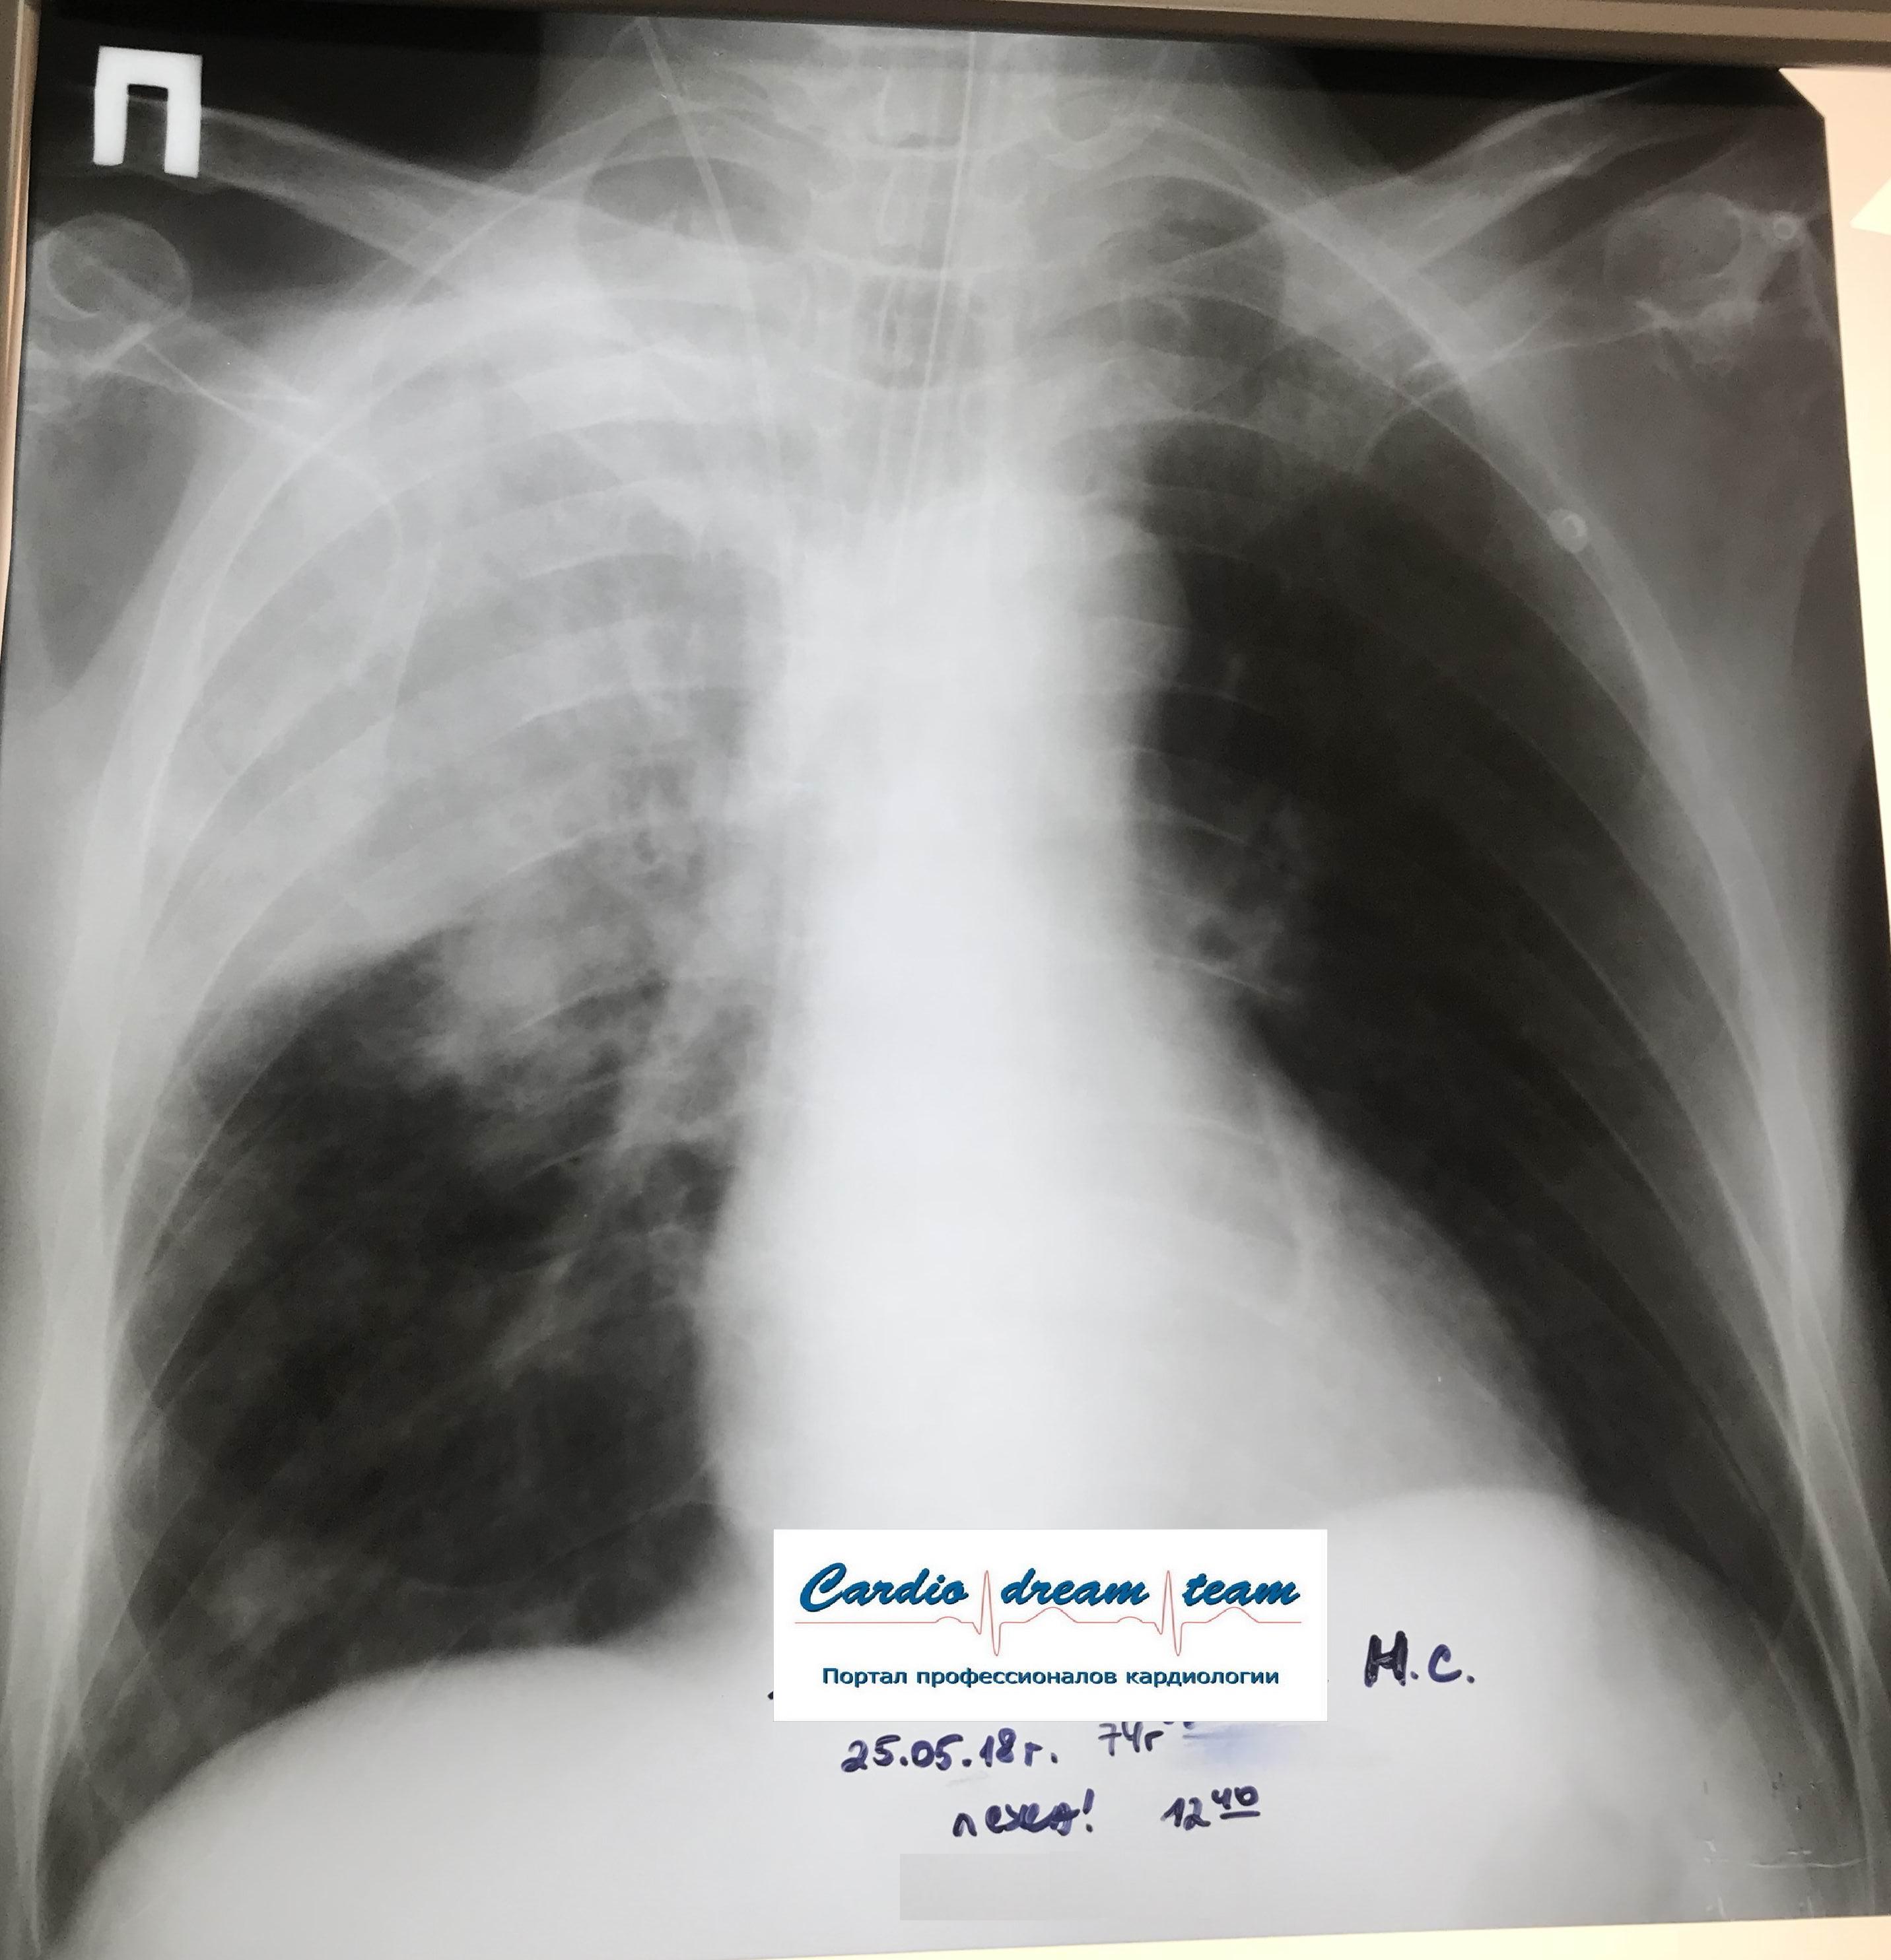

Гиповентиляция механическая - мокротой.

Обсуждалось здесь https://vk.com/club84409679?w=wall-84409679_8127%2Fall